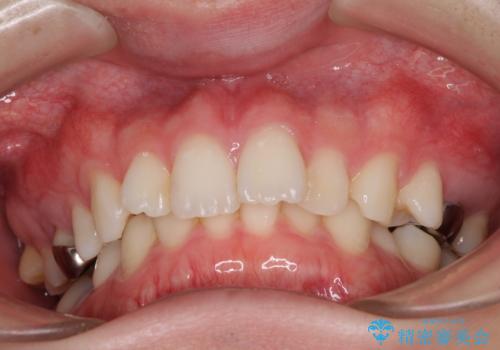

- 咬み合わせと前歯のデコボコを気にして来院された患者様です。

前から5番目の永久歯が3本欠損しており、乳歯が残存している状態でしたが、インビザラインでも十分に対応可能と判断し、インビザラインにて矯正治療を行うこととしました。

右下の残存している乳歯は萌出しきれておらず、全く咬み合っていない状態であり、インビザラインにて移動できない可能性があるため、ワイヤー矯正の併用も念頭に置いて治療を開始しました。